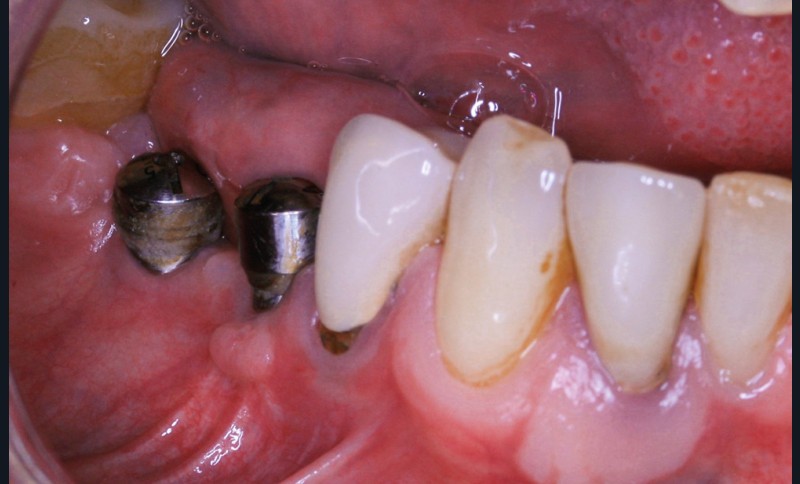

La greffe épithélio-conjonctive (GEC) [7, 8] consiste au remplacement du tissu parodontal existant par un greffon épithélio-conjonctif dont l’indication principale est l’augmentation en hauteur et en épaisseur du tissu kératinisé (fig. 2). Elle peut aussi être utilisée dans le recouvrement radiculaire (avec des résultats en termes de recouvrement inférieurs à ceux des techniques de greffe de conjonctif enfouie), l’aménagement des crêtes édentées, l’aménagement péri-implantaires [9, 10] (fig. 3), ou en association avec un traitement ortho-parodontal [11]. Le principal défaut de cette technique est son aspect inesthétique ; elle sera donc réservée à des zones non visibles comme les incisives mandibulaires ou les zones postérieures.